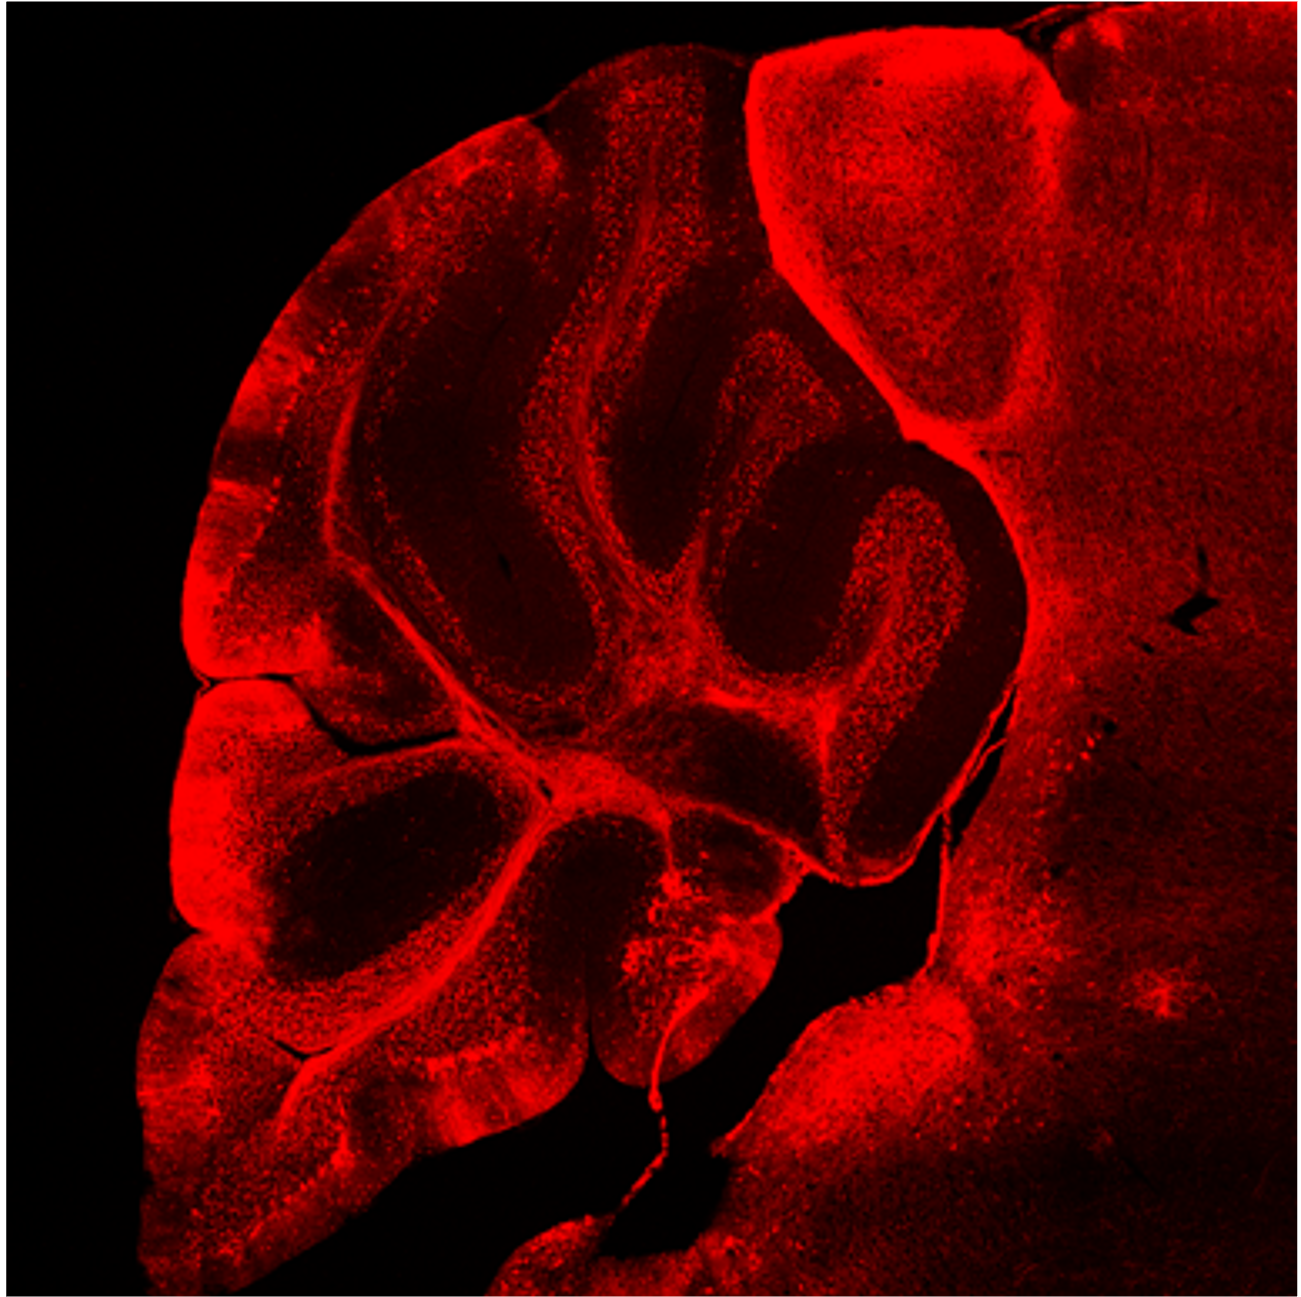

Brain

ATX001

Local delivery results in robust distribution throughout the brain from ICM and ICV injection, with specific targeting of neurons.

Fluorescent microscopy image of a brain cross-section transduced by AAVs expressing RFP.